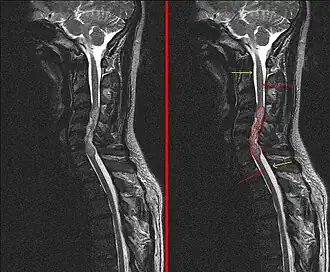

Een MRI zal meestal een tumor nabij de hersenholtes met vergroting van de hersenholtes (hydrocefalus) vertonen. Men maakt een MRI van de hersenen en van de wervelkolom om na te gaan of de tumoren niet verspreid zijn in de hersenen en het ruggenmerg.